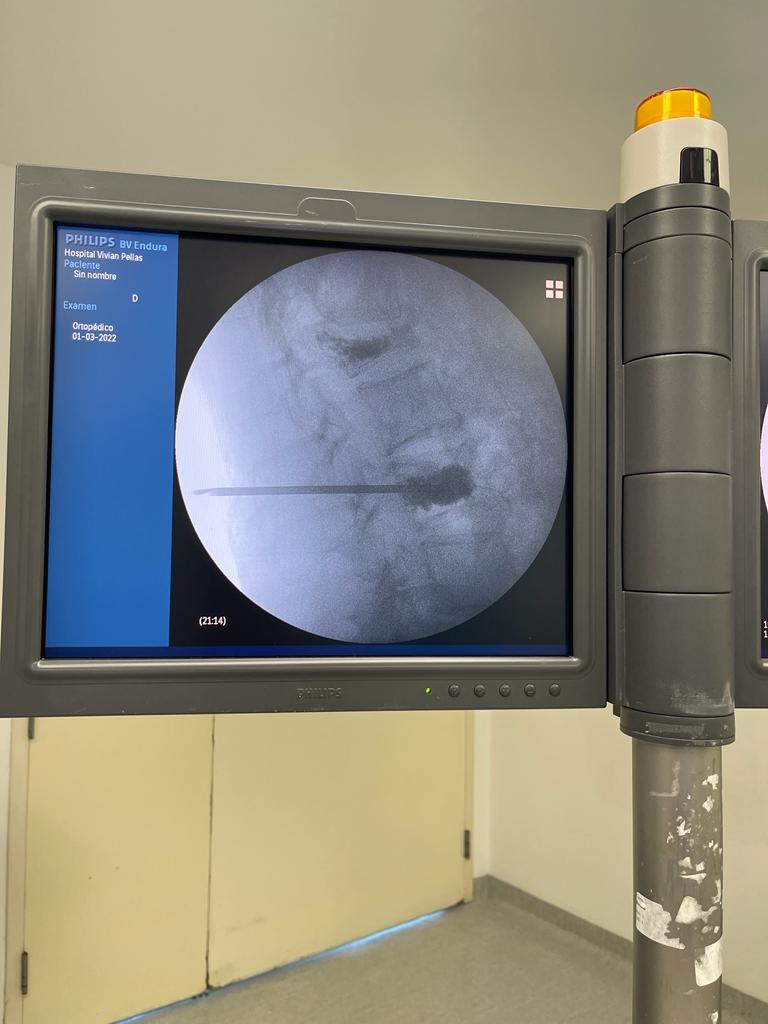

3. Rizólisis (Ablación por radiofrecuencia)

¿Qué es?

Procedimiento no invasivo que utiliza radiofrecuencia para desactivar nervios que transmiten dolor crónico en la columna.

Rizólisis (Ablación por Radiofrecuencia)

Técnica mínimamente invasiva para tratar el dolor crónico articular de la columna

La rizólisis es un procedimiento no quirúrgico que utiliza energía de radiofrecuencia para inactivar de forma selectiva los nervios responsables de transmitir dolor desde las articulaciones facetarias de la columna.